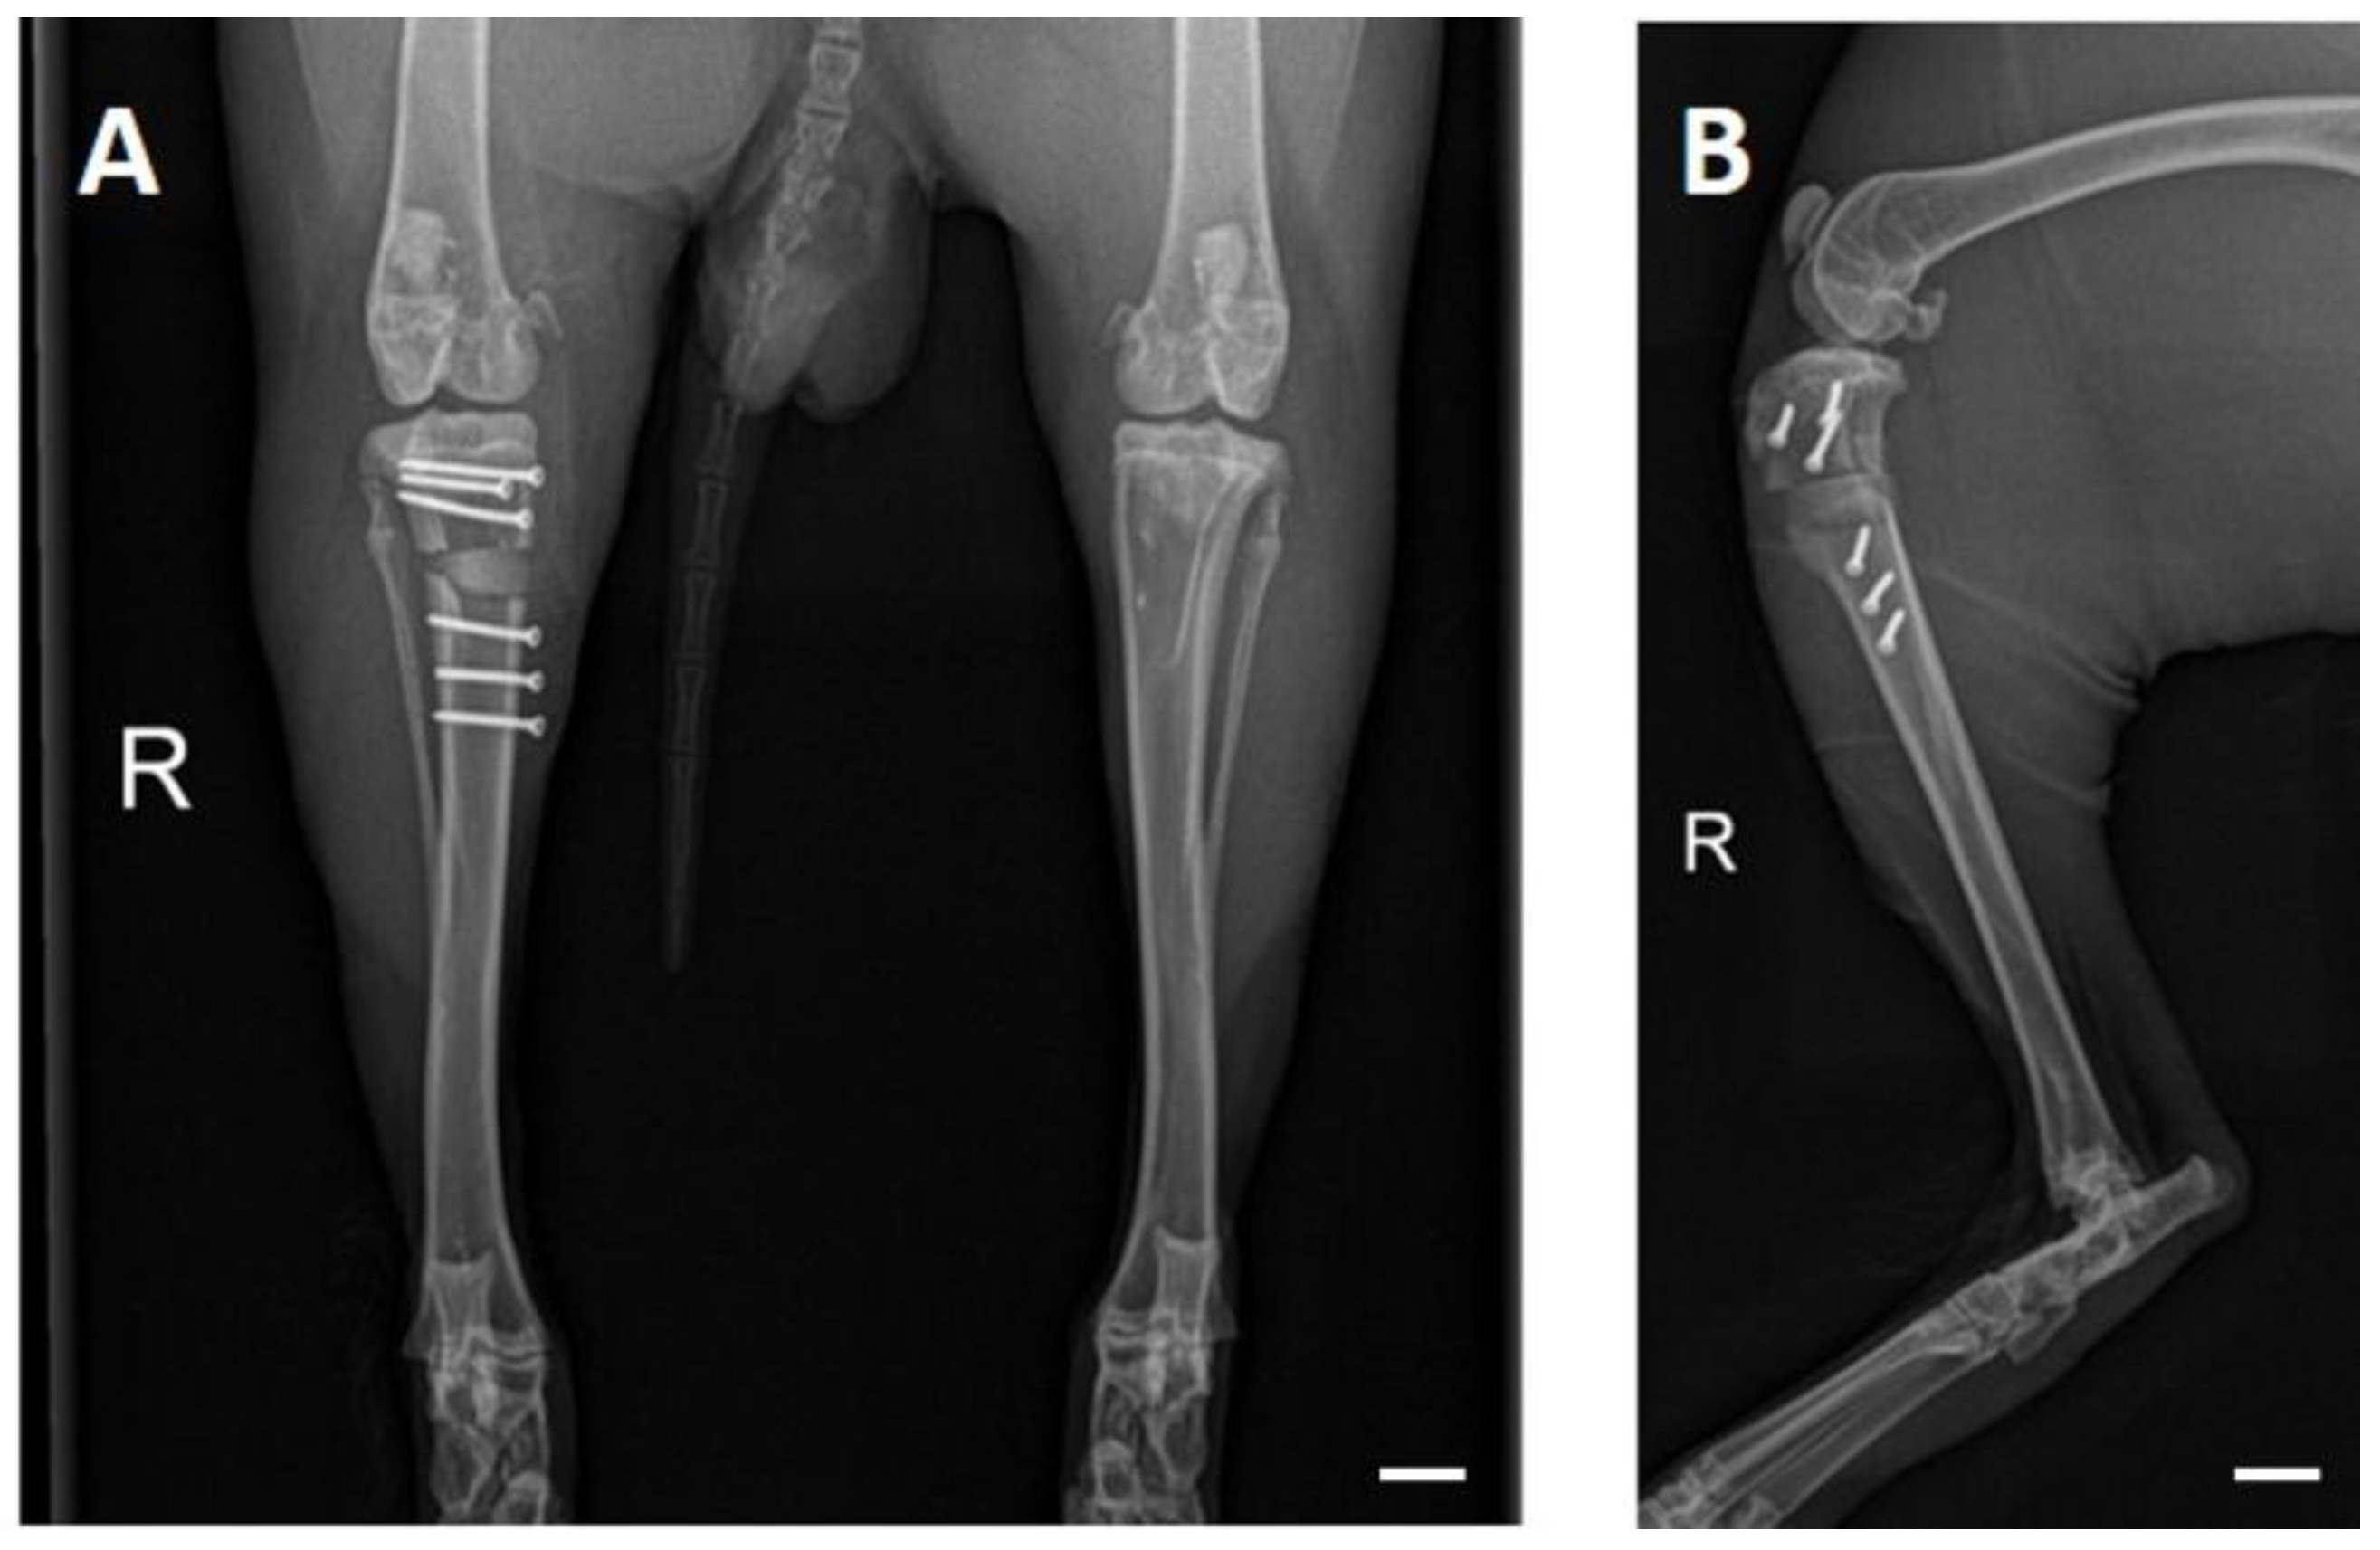

3.3. OP and Clinical Examination

3.4. X-ray Examinations

3.5. In Vivo µCT Examinations